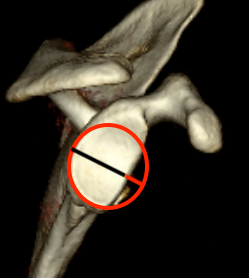

Measurement Hill Sachs

Best fit circle of the articular surface of humeral head

Measure percentage involvement of articular surface

Hill Sachs 30% of the articular surface

Hill Sachs 25% of the articular surface